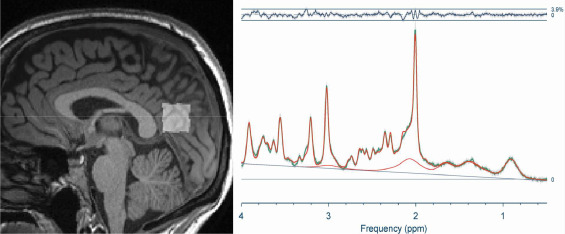

Eine neue Studie (Weber-Fahr et al., 2026) zeigte, dass in bestimmten Hirnregionen von Long COVID-Patienten das Verhältnis von ATP (dem Energie-Molekül) zu Phosphokreatin gestört ist – ein direkter Hinweis auf Energiemangel. Weniger ATP korrelierte mit schlechteren kognitiven Leistungen.

Weber-Fahr-et al., 2026

Weber-Fahr, W.; Dommke, S.; Sack, M.; Alzein, N.; Becker, R.; Demirakca, T.; Ende, G.; Schilling, C. Reduzierte ATP-zu-Phosphokreatin-Verhältnisse bei neuropsychiatrischen Post-COVID-Symptomen: Evidenz aus der 31P-Magnetresonanzspektroskopie. Biological Psychiatry , 2026. https://doi.org/10.1016/j.biopsych.2026.01.004